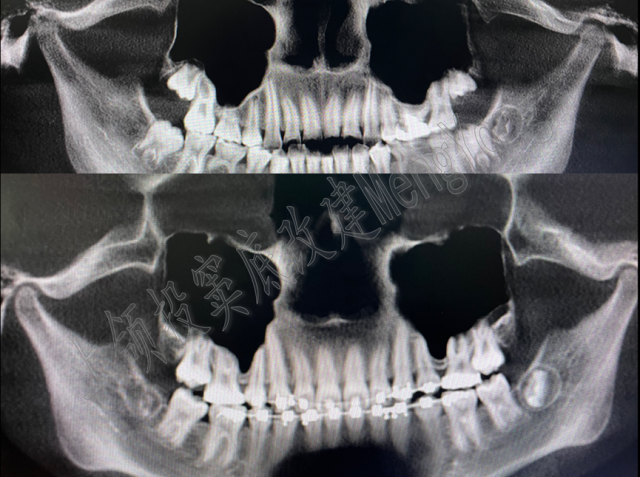

10、 上颌窦底过低的患者的拔牙矫治策略和风险把控